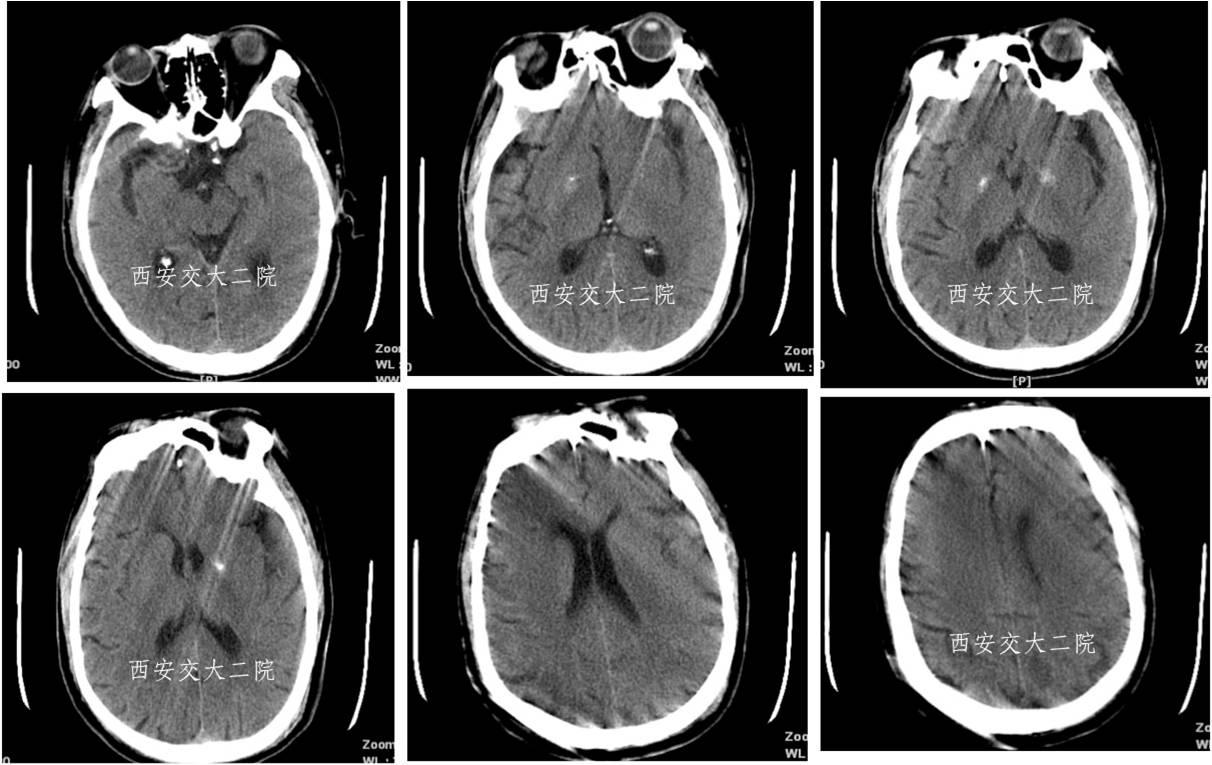

Case 3 大脑中动脉急性闭塞取栓术

》67岁,男;

》有房颤病史,2013.11.25于我院心内住院;

》突然意识不清、左侧肢体瘫痪,言语不能1h;

》查体:嗜睡,混合性失语,双眼向左凝视,双侧瞳孔形圆等大,直径约3mm,对光反射灵敏,右侧肢体肌力0级。

急诊脑CT

取栓后即刻脑CT及临表

术后24h脑CT及临表

术后4天脑CT及临表

术后2周脑CT及临表